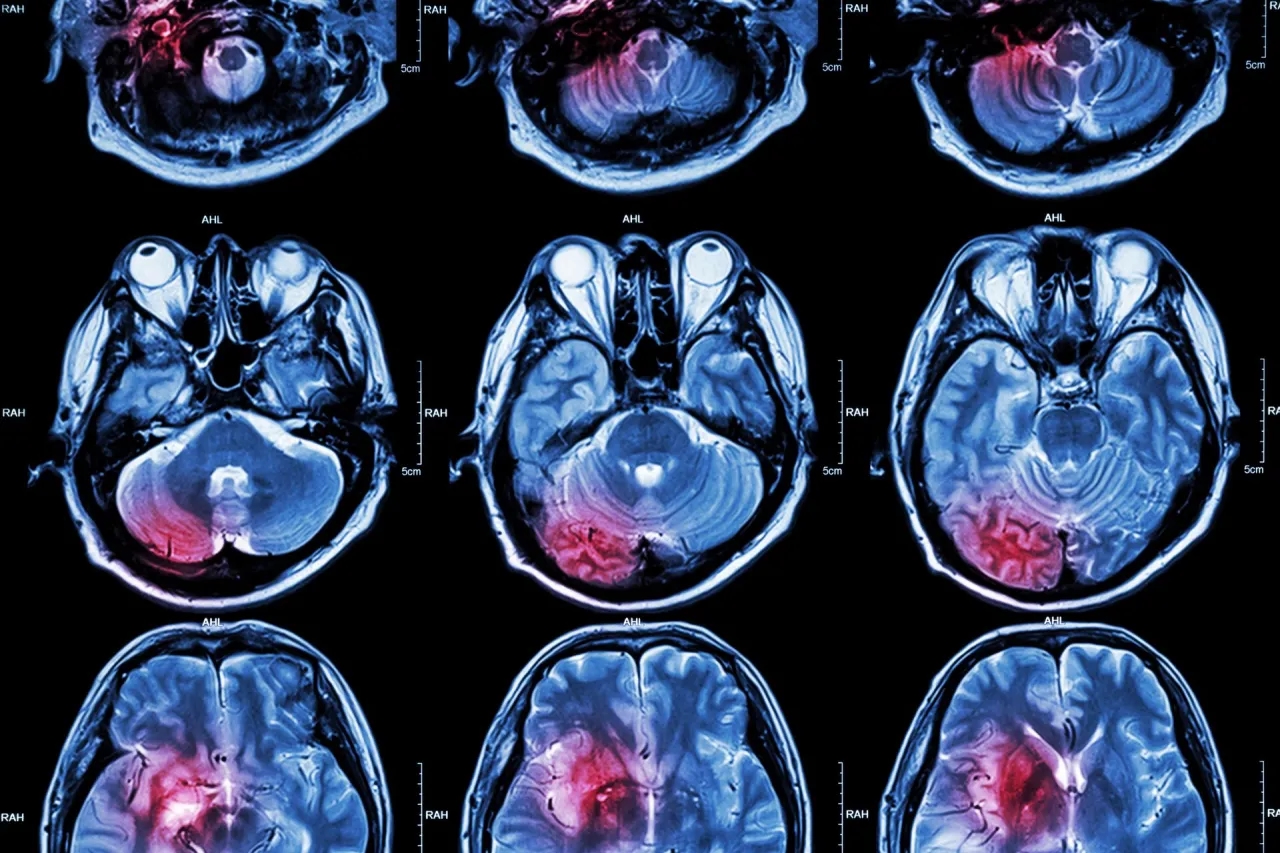

Pierwsze objawy udaru to sygnały, które pojawiają się nagle i mogą wskazywać na uszkodzenie mózgu. Należą do nich m.in. asymetria twarzy, trudności w mówieniu czy osłabienie mięśni. Te symptomy są wynikiem zaburzeń w przepływie krwi do mózgu, co prowadzi do niedotlenienia komórek nerwowych.

Ignorowanie tych objawów może mieć poważne konsekwencje. Udar mózgu to stan bezpośredniego zagrożenia życia, a opóźnienie w leczeniu zwiększa ryzyko trwałego uszkodzenia mózgu. Szybka reakcja może uratować zdrowie, a nawet życie – dlatego pierwsze objawy udaru nigdy nie powinny być bagatelizowane.Jak rozpoznać wczesne objawy udaru – kluczowe symptomy